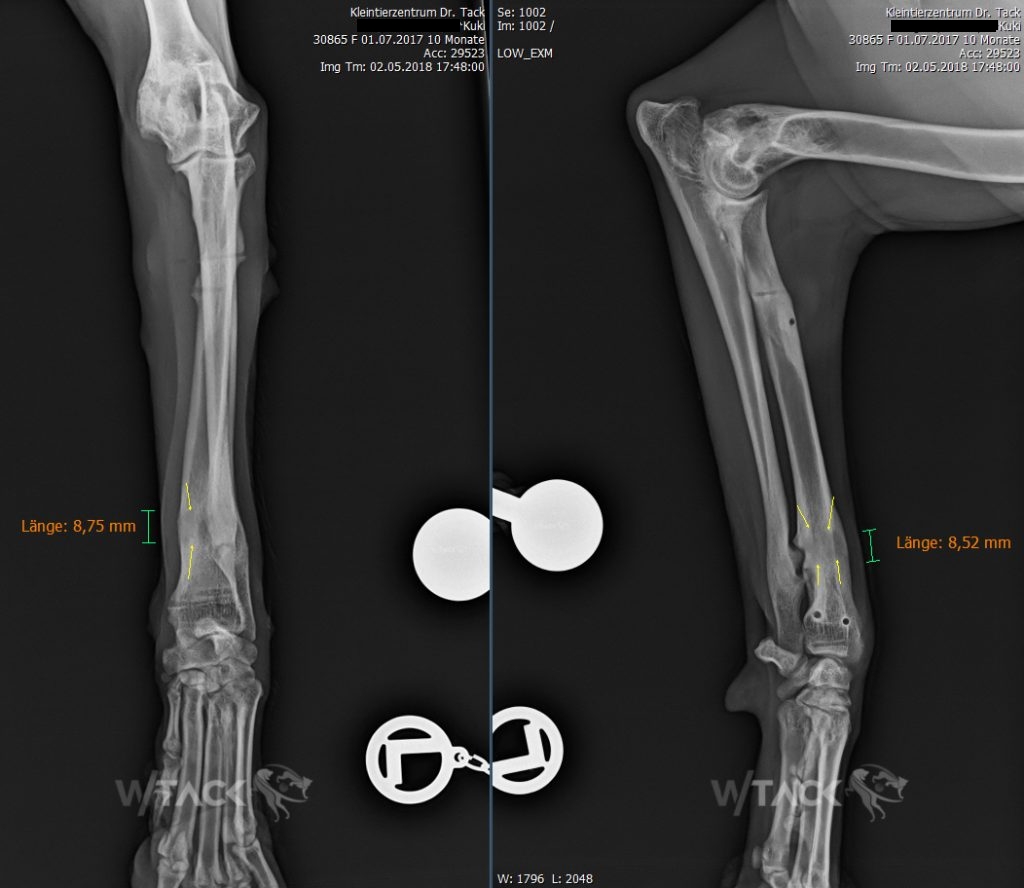

Kuki wurde im Alter von 5,7 Monaten durch einen Autounfall verletzt. Durch vorzeitigen Schluss der Radius (Speiche) Wachstumsfugen bildete sich eine Stufe im Ellbogengelenk. Dadurch kommt es zu einer Lahmheit, Schmerzen und Arthroseentwicklung.

Um die Kongruenz des Ellbogelenks wiederherzustellen verlängerten wir den Radius mit einem Ringfixateur um 1mm pro Tag (Knochenverlängerung – Distraktionsosteogenese).